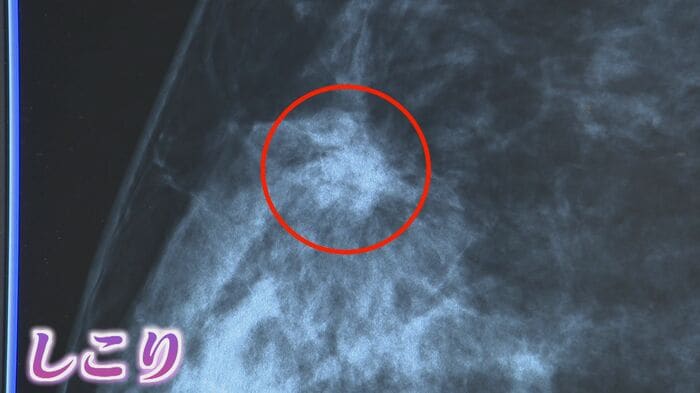

乳がん検診は主に乳房専用のX線撮影『マンモグラフィー』で行われる。ホルモンバランスの影響を受けやすい40代と閉経後に肥満傾向になりやすい60代で発症するケースが多く、国の指針では40歳から2年に1度の定期的な検診が推奨されている。

早期発見のきっかけになる代表的な症状が“しこり”だ。山田舞医師によると、2センチ以下がステージⅠになるという。